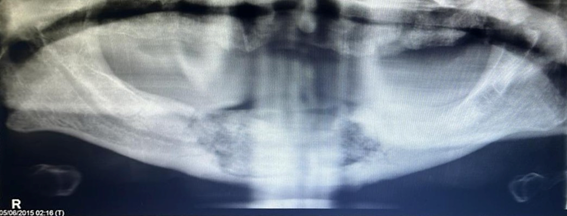

A panoramic radiograph was indicated where a radio-lucent area was observed in the anterior sector of the mandible compatible with bone destruction and bone sequestration that ranged from the aforementioned area to the premolar region in the middle portion of the mandible. (Figure 1)

Figure 1 Panoramic view showing radiolucent area in the anterior sector of the mandible.